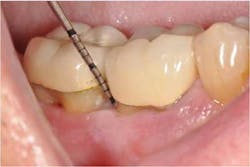

In the present case, a 61-year-old male was referred to my periodontal office by his general dentist for an evaluation of pain and bleeding to the lower right mandible. The patient’s medical history consisted of controlled type 2 (noninsulin dependent) diabetes and hypertension. Upon review of the panoramic radiograph (figure 1), the periodontal defects are not clearly evident, thus showing the importance of proper radiographs to detect periodontal defects. The periapical radiographs (figure 2) clearly show subgingival calculus, grade 1 furcation on No. 30, grade 3 furcation on No. 31, and an advanced intrabony defect on the distal of No. 30. Clinically, there was no mobility to either No. 30 or 31 and both teeth were vital. Tooth vitality is an extremely important diagnostic factor in treatment panning. Periodontal charting of the lower right was also performed, and the lower right exhibited bleeding and inflammation (figure 3).

The patient returned for a postop appointment at 5.5 months and a new radiograph (figure 5) and clinical photographs (figures 6 and 7) were taken. Excellent regeneration is evident at both sites radiographically and clinically. New periodontal charting was done (figure 8) showing near-complete regeneration of the intrabony defect on the distal of No. 30 and a great improvement in the furcation of No. 31. There is no bleeding or inflammation present at this time.